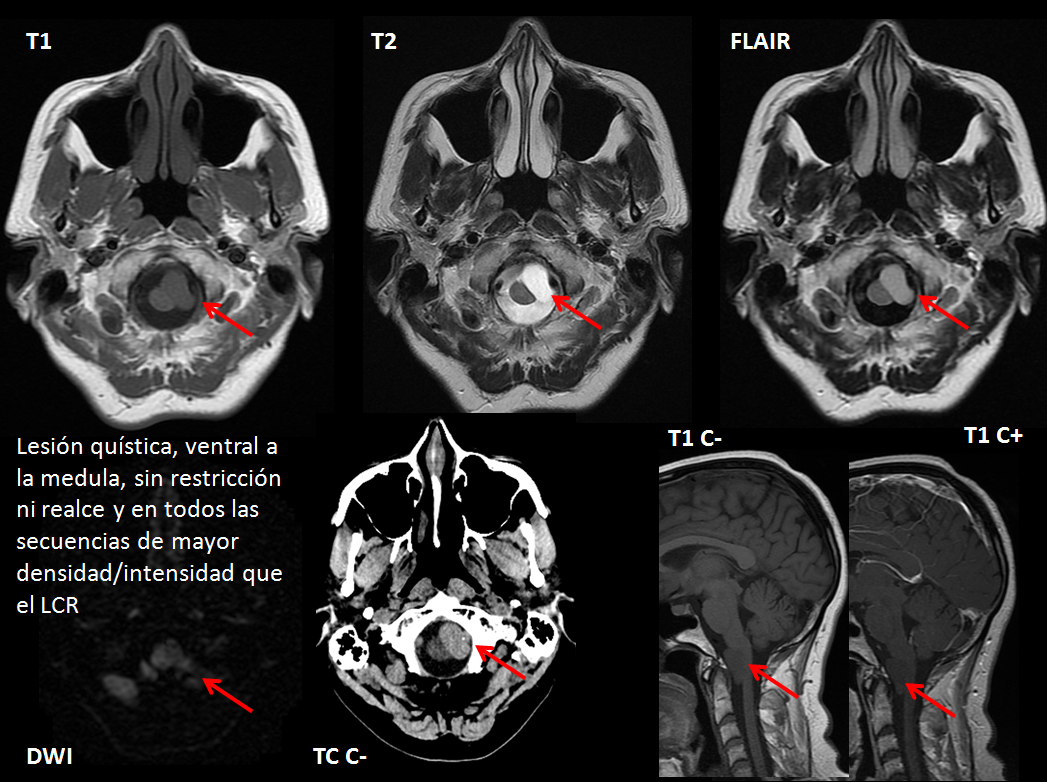

Paciente de 46 años de edad, asintomático. Se le realizo TC debido a traumatismo, posterormente se amplio estudio mediante RM.

Su localización más frecuente es en la columna vertebral a nivel a intradural-extramedular (80% de los casos), ventrales a la medula espinal en la línea media (más frecuentes en el segmento cervicotorácico de la columna vertebral); a nivel intracraneal es extremadamente raro aunque es más frecuente en la fosa posterior, de nuevo en la línea media ventral al tallo cerebral o en el ángulo pontocerebeloso.

En TC sus características son variables, aunque general mente es más denso que el LCR; sus características dependen del grado de contenido proteináceo.

Respecto al LCR la mayoría son iso-hiperintensos en T1 y típicamente hiperintensos en T2 y FLAIR. Pueden no tener restricción en DWI o mostrarla en grado leve. Generalmente no muestran realce tras administrar contraste intravenoso.